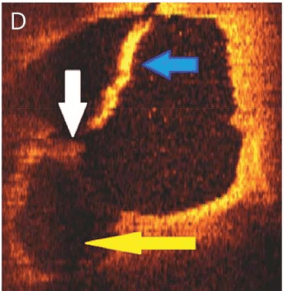

Histopathology & OCT

Choi PM AJNR Am J Neuroradiol. 2015 .Christopher R. Pasarikovski, Neurology: Clinical Practice 2019

How does it appear in carotid angiogram and in real time per-operative ?

Images : Chen H, Colasurdo M, Costa M, Nossek E, Kan P. Carotid webs: a review of pathophysiology, diagnostic findings, and treatment options. J Neurointerv Surg. 2024 Nov 22;16(12):1294-1298. doi: 10.1136/jnis-2023-021243. PMID: 38290814.